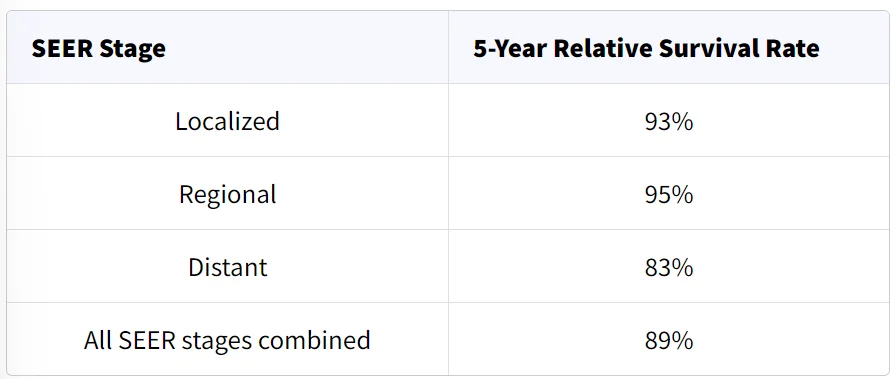

میزان بروز لنفوم هوچکین از اواسط دهه 2000 حدود 1 درصد در سال کاهش یافته است. میزان بقا در چند دهه گذشته بیشتر به دلیل پیشرفت در درمان بهبود یافته است. نرخ بقای نسبی 5 ساله برای همه بیماران مبتلا به لنفوم هوچکین در حال حاضر حدود 89 درصد است. عوامل خاصی مانند مرحله (وسعت) لنفوم هوچکین و سن فرد بر این میزان تأثیر میگذارد.

میزان بقا برای لنفوم هوچکین

میزان بقا میتواند به شما این ایده را بدهد که چند درصد از افراد مبتلا به همان نوع و مرحله سرطان تا مدت معینی (معمولاً 5 سال) پس از تشخیص هنوز زنده هستند. آنها نمیتوانند به شما بگویند که چقدر زنده خواهید ماند اما ممکن است به شما کمک کنند تا درک بهتری در مورد احتمال موفقیت روند درمان خود داشته باشید.

به خاطر داشته باشید که میزان بقا تخمینی است و اغلب بر اساس نتایج قبلی تعداد زیادی از افرادی است که سرطان خاصی داشتند اما آنها نمیتوانند پیش بینی کنند که در مورد فرد خاصی چه اتفاقی خواهد افتاد.

این آمار میتواند گیج کننده باشد و ممکن است شما را به پرسیدن سوالات بیشتری سوق دهد. از پزشک خود که با شرایط شما آشنایی دارد، بپرسید که چگونه این اعداد ممکن است برای شما اعمال شوند.

نرخ بقای نسبی 5 ساله چیست؟

نرخ بقای نسبی، افراد با همان مرحله لنفوم هوچکین را با افراد موجود در کل جمعیت مقایسه میکند. به عنوان مثال، اگر میزان بقای 5 ساله برای مرحله خاصی از لنفوم هوچکین 80 درصد باشد، به این معنی است که احتمال زنده مانی افرادی که به آن سرطان مبتلا هستند برای ۵ سال پس از تشخیص ابتلا به بیماری نبست به افرادی که به آن سرطان مبتلا نیستند، به طور متوسط 80 درصد است.

این اعداد از کجا میآیند؟

انجمن سرطان آمریکا برای ارائه آمار بقای انواع مختلف سرطان به اطلاعات پایگاه داده نظارت، اپیدمیولوژی و نتایج نهایی (Surveillance, Epidemiology, and End Results یا SEER) که توسط موسسه ملی سرطان (National Cancer Institute یا NCI) نگهداری میشود، متکی است.

پایگاه داده SEER نرخ بقای نسبی 5 ساله لنفوم هوچکین در ایالات متحده را بر اساس میزان گسترش سرطان دنبال میکند. با این حال پایگاه داده SEER سرطانها را بر اساس طبقه بندی لوگانو (مرحله 1، مرحله 2، مرحله 3 و غیره) گروه بندی نمیکند. در عوض، سرطانها را به مراحل موضعی، منطقه ای و دور دسته بندی میکند:

- موضعی (Localized): سرطان به یک ناحیه غدد لنفاوی، یک اندام لنفاوی یا یک اندام خارج از سیستم لنفاوی محدود میشود.

- منطقه ای (Regional): سرطان از یک ناحیه غدد لنفاوی به اندام مجاور میرسد، در دو یا چند ناحیه غدد لنفاوی در یک سمت (بالا یا پایین) دیافراگم یافت میشود یا به عنوان بیماری حجیم در نظر گرفته میشود.

- دور (Distant): سرطان به قسمتهای دورتر بدن مانند ریهها، کبد یا مغز استخوان یا به نواحی غدد لنفاوی بالا و زیر دیافراگم گسترش یافته است.

نرخ بقای نسبی 5 ساله برای لنفوم هوچکین

این اعداد بر اساس اطلاعات افرادی است که بین سالهای 2012 تا 2018 به لنفوم هوچکین مبتلا شده اند.

درک اعداد

- این اعداد فقط برای مرحله سرطان در هنگام اولین تشخیص صدق میکند. اگر سرطان رشد کند، گسترش یابد یا پس از درمان عود کند، بعداً اعمال نمیشوند.

- این اعداد همه چیز را در نظر نمیگیرند. میزان بقا بر اساس میزان گسترش سرطان گروه بندی میشود اما سن و سلامت کلی شما، میزان پاسخگویی لنفوم به درمان و سایر عوامل پیش آگهی (که در زیر توضیح داده شده است) نیز میتوانند بر دیدگاه شما تأثیر بگذارند.

- افرادی که اکنون مبتلا به لنفوم هوچکین تشخیص داده شده اند، ممکن است چشم انداز بهتری نسبت به این اعداد داشته باشند. درمانها در طول زمان بهبود یافته اند و این اعداد بر اساس اطلاعات افرادی است که حداقل 5 سال زودتر تشخیص داده شده و درمان شده اند.